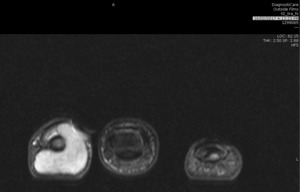

Examination revealed a 20-millimetre, non-tender, ulcerated paronychial mass lifting the nail plate (Figure 1). Distal tip sensation was intact. X-ray showed cortical thinning of distal phalanx consistent with extrinsic compression. MRI noted two separate but communicating lesions, which almost circumferentially enclosed the distal phalanx (Figure 2).